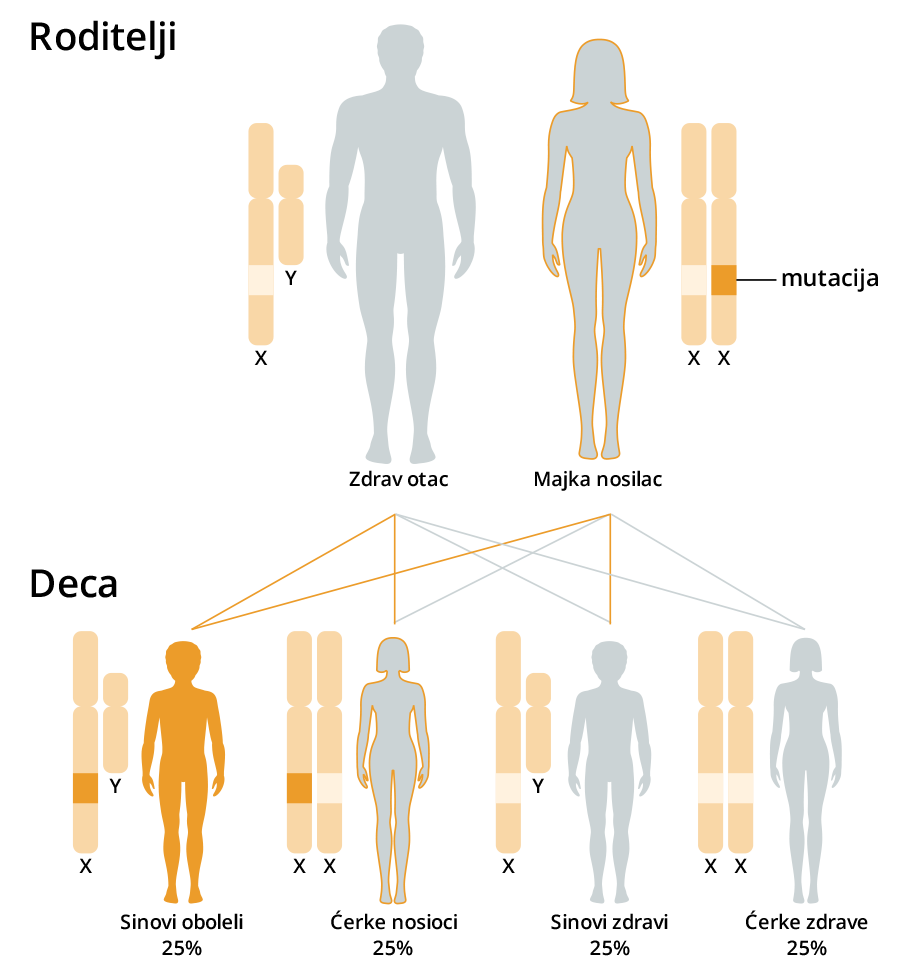

Testom se vrši skrining autozomno recesivnih, autozomno dominantnih i bolesti povezanih sa X hromozomom.

Većina dece sa naslednim oboljenjima se rađa zdrava, a prvi simptomi bolesti se javljaju tek nakon nekoliko nedelja ili meseci, dok su roditelji ugavnom potpuno zdravi i bez ikakvih tegoba.

Kod dominantnih bolesti RIZIK ZA DECU JE 50% ILI VEĆI I ZAVISI OD STATUSA RODITELJA.